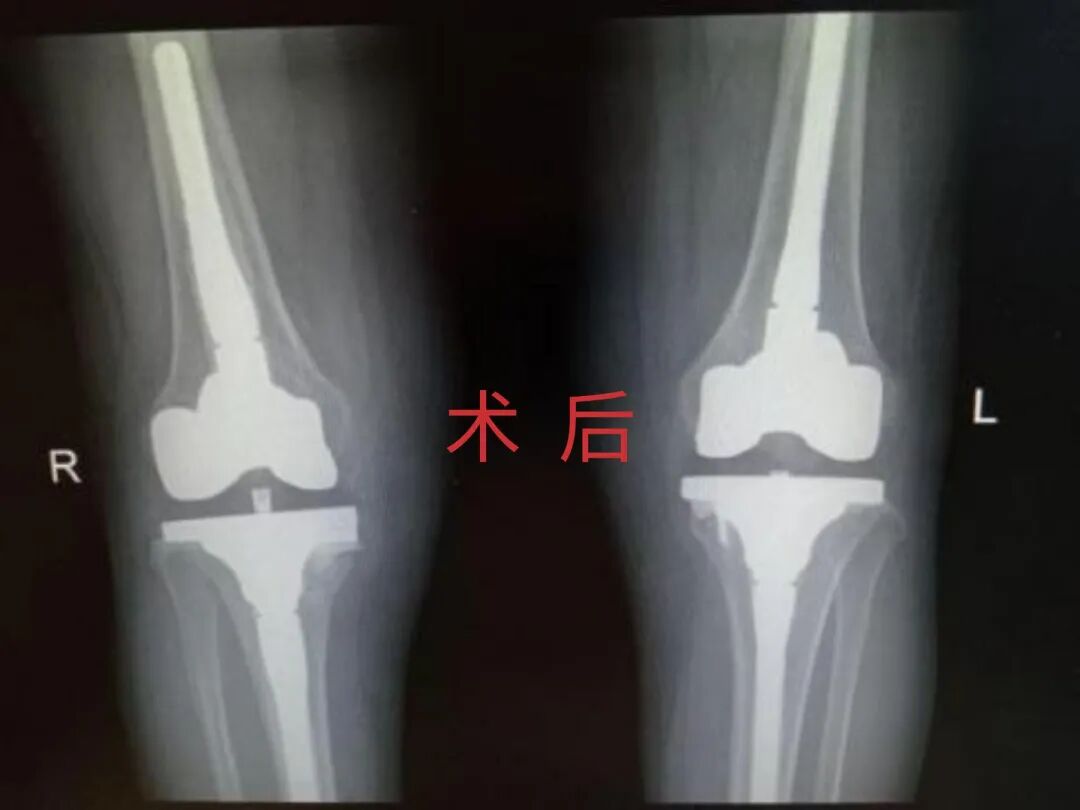

多年来,贵州航天医院各科室紧跟医学前沿,不断强技术、补短板,大力开展新技术、新项目,完成了许多高精尖、高难度、本地区“首例”的技术,填补了医院医疗技术空白,满足了群众日益增长的医疗需求。 贵州航天医院骨科率先在遵义地区开展骨搬移技术,截至目前,已治愈慢性骨髓炎、感染性骨不连、骨缺损、脉管炎、糖尿病足患者200余例,糖尿病足治疗保肢率达到98%。 本期,我们将为大家带来骨科特色技术——骨搬移技术(Ilizarov)。 案例分享 一名59岁的患者,身患糖尿病12年,在来我院3个月前出现了右脚溃烂的症状,来院就诊时,患者的右脚十分红肿,右脚脚趾坏死,伤口处不断流出黑红色脓液,情况十分严重。在接诊到患者时,骨科专家团队高度重视,立刻为患者完善了CT血管造影(CTA)等相关检查,诊断为:2型糖尿病,糖尿病周围血管病变,右糖尿病足。 术 前 考虑到患者情况比较严重,为最大限度保证患者肢体完整,科室专家团队进行了严格的讨论评估,为患者制定了骨搬移技术治疗方案,在征得患者及其家属的同意后,成功通过搬移骨块为患者进行治疗,促进患者病变肢体血管再生。 胫骨横向骨搬移外架固定 清除感染病灶 术后调节外架,通过搬移骨块 促进患肢血管再生 患者在术后三周前来换药,观察到感染得到进一步控制;术后六周复查,患者病变处已愈合,进行CT血管造影(CTA)后可明显观察到足部血管再生。 术后3周 术后6周愈合 CT血管造影见足部血管再生 糖尿病患者全身与局部的问题互为影响,形成恶性循环,糖尿病足溃疡创面迁延不愈,常见干性坏疽、湿性坏疽、趾坏死、深且大的溃疡以及骨髓炎等症状,还可导致脓毒血症,以往为保全生命,患者被迫选择一次或多次截肢。骨搬移技术的发展进步,能在血糖有效控制、局部有效清创下,有效促进患肢微血管再生,改善患肢血供,达到糖尿病足更快治疗康复的目的,并能根据病变情况最大限度的保障患者肢体完整。 什么是骨搬移技术 骨搬移技术是通过使用专用的骨外固定器固定骨段,每天缓慢牵拉,在牵拉搬移过程中,骨段尾部形成新骨及新的软组织,从而修复骨骼缺损及软组织缺损。是治疗大段骨缺损、骨不连、骨感染、肢体畸形的金标准方法,也用于治疗脉管炎、糖尿病足等肢体缺血性疾病。 骨感染缺损 切除感染段 搬移骨段 新骨形成 骨感染根治愈合 骨搬移技术原理 生物组织在持续、稳定、缓慢牵拉下,能刺激细胞分裂、组织再生,骨外固定技术运用该原理,通过持续缓慢调节外固定器形成牵拉张力,促进牵引成骨与相邻组织再生,如神经、血管、肌肉、皮肤等再生,达到治疗大段骨缺损、肢体缺血如糖尿病足等疾病的目的。 骨搬移技术优势 (一)除治疗骨缺损、骨不连外,有更广的适用范围,利用组织再生、血管再生等特性,能大量运用于肢体畸形的矫形、糖尿病足等的治疗。 (二)治疗效果确切,重建肢体外型和功能,极大降低截肢率和残疾率。 (三)明显提高了患者生活质量,极大减轻其家庭及社会负担。 肢体畸形的矫形 慢性骨髓炎 骨段切除 术后1年 濒临截肢的脉管炎术后6周 难愈创面术后3周 贵州航天医院骨科 专家团队 赵学平 骨科主任 主任医师 临床擅长:从事骨科临床工作30余年,对骨科常见疾病的诊治具有丰富的临床经验。 世界中医药联合会脊柱康复专业委员会常务理事,中华中医药学会整脊分会常务委员,中国中西医结合学会骨伤科分会肢体矫形功能重建与康复专家委员会常务委员,中国研究性医院学会骨科创新与转换专业委员会关节外科学组保髋工作委员会常委,中国康复技术转化及发展促进会骨外科与康复技术转化专业委员会常务委员,泛珠三角区域运动医学联盟(PPRD-SMA)理事会常务理事,中国研究型医院学会运动医学专业委员会委员,贵州省中医药学会整脊分会副主任委员,贵州省中西医结合学会银质针专业委员会副主任委员,贵州省康复医学会骨与关节专业委员会常务委员,贵州省人民医院骨科专科联盟常务理事,贵州省康复医学会骨内科专业委员会常务委员,中华医学会贵州省骨科学会委员,贵州省康复医学会脊柱脊髓专业委员会常务委员,贵州省运动医学分会委员,贵州省康复医学会骨与软组织肿瘤专业委员会委员,遵义市医学会创伤分会副主任委员,贵州省康复医学会骨内科专业委员会遵义地区分会常务委员,遵义市医疗事故鉴定、伤残鉴定、工伤鉴定、司法鉴定专家。 长期从事骨科临床研究及教学工作,在国家级、省部级杂志发表论文20余篇,SCI论文2篇,参与主编骨科专著2部,主持省部级科研项目2项,参与指导省部级、市级科研项目6项。 陈明勇 骨科副主任 副主任医师 临床擅长:从事创伤骨科工作约20年,对骨缺损、骨不连、骨肿瘤、肢体畸形等的肢体矫形重建及功能重建,慢性化脓性骨髓炎的根治治疗、糖尿病足的保肢治疗、快速康复理念(ERAS)下的老年骨折的诊治,四肢复杂骨折的诊治,四肢骨折等微创手术治疗具有丰富的临床经验。 2004年毕业于遵义医学院临床专业,曾在中国人民解放军总医院、广西医科大学第一附属医院、上海第六人民医院骨科进修。中国中西医结合学会骨伤科专业委员会横向骨搬移治疗糖尿病足及微血管网再生学组首届委员,遵义市医学会创伤分会常务委员。 瞿 辉 骨科 副主任医师 临床擅长:对骨科的常见病、关节外科、脊柱外科及运动医学疾病的诊治具有丰富的临床经验,熟练掌握骨科手术操作技术。 毕业于遵义医学院临床医学系,2005年前往广州中山大学第一附院骨显微医学部进修学习,2011年前往成都华西医院进修学习,并多次在省内外学习骨科相关知识,是中华医学会骨科分会会员。 赵兴东 骨科 主任医师 临床擅长:擅长骨科的常见病及各种创伤、四肢骨折创伤修复、骨感染、手足疾病的诊治和手足体表畸形的矫形整复,熟练掌握骨科四肢骨病及创伤的手术操作技术,尤其在四肢关节复杂性损伤、手足外伤、组织缺损创面、难治创面的皮瓣修复方面及平足、高弓足矫形方面及四肢慢性疼痛诊治、康复方面具有丰富的临床经验。 硕士研究生,毕业于遵义医学院临床外科系,2015年前往山东省立医院手足外科进修学习;遵义市医学分会创伤分会第一、二届委员,遵义市手外科医学会第二委届员会常务委员;在省级及省级以上期刊发表文章9篇,参编著作2部,参与主持并完成市级课题1项,参与市级课题2项、省级课题1项。 张俊凯 骨科 副主任医师 临床擅长:从事骨科临床工作28年,对创伤骨折、骨感染、骨缺损、骨不连等外科诊治,四肢骨折的微创手术治疗,四肢复杂骨折(如关节内粉碎性骨折、多发骨折等)的损伤控制及手术治疗等具有丰富的临床经验。 1995年毕业于遵义医学院临床专业,2009年前往复旦大学附属医院骨科进修1年。 卢懿明 骨科 副主任医师 临床擅长:从事骨科工作18年,对创伤骨折、四肢骨折的微创手术治疗、四肢复杂骨折(如关节内粉碎性骨折、多发骨折等)的损伤控制及手术治疗,尤其是髋部骨折的PFNA等微创技术,踝关节骨折、膝关节周围骨折的Mipo微创技术等具有丰富的临床经验,开展了4项新技术,发明6项新型专利技术。 2005年毕业于遵义医学院临床专业,2017年,前往南方医科大学第三附属医院骨科进修半年,回院后运用Mipo技术对骨干骨折及干骺端骨折的治疗技术,同时积极开展骨盆骨折、髋臼骨折腹直肌外侧切口的应用;发表了多篇专业论文,经常参与省内外学术交流会授课,获得医院荣誉称号多个。 邬夏荣 骨科 副主任医师 临床擅长:从事骨科工作16年,对四肢复杂骨折、骨肿瘤的诊治,尤其是足踝创伤、慢性踝关节损伤、平足症等诊疗具有丰富的临床经验。 2006年毕业于遵义医科大学临床医学专业,曾在陆军军医大学西南医院进修学习,发表多篇骨科学术论文。 余德怀 骨科 副主任医师 临床擅长:从事骨科工作10余年,对运动医学、骨关节、脊柱外科常见病、多发病的诊治具有丰富的临床经验。 硕士研究生,2011年毕业于遵义医学院临床医学专业,曾前往遵义医科大学附属医院运动医学专业进修学习;是贵州省医学会运动医学分会青年委员,西部关节镜联盟委员;发表多篇骨科学术论文。 冯 乾 骨科 副主任医师 临床擅长:从事骨科工作近20年,熟练掌握骨科多发病及常见病的诊治,尤其对脊柱退变性疾病的诊断及治疗具有丰富的临床经验,主要研究脊柱微创相关治疗方式,能熟练开展椎间孔镜及VBE。 曾前往北京大学第三医院进修学习疼痛及椎间孔镜、首都医科大学友谊医院专业进修脊柱内镜;是贵州省康复医学会第三届脊柱脊髓专业委员会委员;发明专利3项、发表脊柱外科专业论文多篇。 张艳金 骨科 副主任医师 临床擅长:从事骨外科工作16年,对复合伤、多发伤的救治、四肢骨干骨折、关节周围骨折、骨肿瘤、骨髓炎等诊治具有丰富的临床经验。 中共党员,硕士研究生,2006年本科毕业于山西医科大学第二临床医学院,2011年研究生毕业于北京军区总医院;在“老年COPD患者合并髋部骨折的诊治”国际合作课题组研究两年,在老年髋部骨折的诊治方面具有丰富的经验,并发表论文6篇;承担遵义市级课题1项;承担遵义医科大学的临床教学工作,获得遵义医科大学优秀带教老师荣誉。编撰有《骨科疾病诊疗精粹》一书,开展2项新技术,编撰地方规范《务川自治县创伤骨科常见疾病诊疗规范》一书。 赵小锋 骨科 副主任医师 临床擅长:从事骨科临床工作11年,对骨科常见病、多发病诊疗有较为丰富的临床经验,擅长脊柱相关疾病诊断及治疗,尤其是颈、腰、腿疼痛疾病诊断及治疗,擅长胸腰椎骨折微创经皮穿刺内固定术、经皮穿刺椎体成形术、经皮穿刺脊柱内镜下腰椎间盘摘除术、单纯开创腰椎间盘摘除术、腰椎滑脱复位椎间植骨椎融合内固定术、腰椎管狭窄减压融合内固定术及人工髋、膝关节置换术等。 2012年毕业于遵义医学院外科学专业硕士研究生,2019年参加“遵义市115医学人才精英计划”于上海交通大学第一附属医院培训学习,2023年于北京大学第三人民医院脊柱外科进修学习,曾获得遵义市优秀医师荣誉称号。 遵义市手外科第一届委员,遵义市医学会创伤分会第一届委员,遵义市医学会创伤分会第二届委员,贵州省康复医学会第三届脊柱脊髓专业会委员,遵义市医学会烧伤与整形外科学分会委员,发表论文5篇,其中国家级核心期刊1篇,SCI论文1篇,主持市级课题1项并结题,参与市级课题2项。 贵州航天医院骨科简介 基本情况 贵州航天医院(原3417医院)骨科组建于1968年,前身是以创伤和断肢(断指)再植闻名于世的上海市第六人民医院骨科,中国断肢(断指)再植的奠基者、中科院院士陈仲伟等著名专家、学者多次莅临科室指导医疗、教,是贵州省最早拥有专业骨科技术科室之一,在70年代开展了贵州省首例断肢(断指)再植手术。组建50余年来,诊治患者已逾百万,挽救了无数的伤病员,成为了保障遵义地区人民群众健康的重要支撑。 经过几代人的不懈努力,今天的骨科,已由创伤骨科发展至骨病、骨肿瘤、骨结核等领域,现有脊柱外科、关节外科、四肢创伤、手足外科四个亚专科,成为了集医疗、教学、科研于一体的综合学科,是贵州省临床重点专科、遵义市临床重点专科、遵义市骨科临床医学中心、遵义市基层骨科专科联盟理事长单位。 科室目前开放床位110张,共有医护人员50余人,副高级以上专家18人,硕士研究生15人。拥有一流骨科医疗设备多台,每年不定期选派优秀技术骨干到全国各大知名医学院校进修、学习、参观、交流,并邀请国内、国外知名专家教授来院进行交流、指导,通过不断引进国内外先进的诊疗技术,科室医疗技术水平稳步提升,为广大人民群众提供了优质的医疗服务。 专科特色 骨一科 (一)骨缺损、骨不连的肢体与功能重建 胫骨横向骨搬移技术治疗糖尿病足: (二)慢性骨髓炎的根治治疗 (三)肢体缺血性疾病如糖尿病足、脉管炎的保肢治疗 (四)皮瓣修复 (五)复杂创伤的治疗 (六)老年髋部骨折及小儿骨折快速手术 老年髋部骨折: 骨二科 (一)胸腰椎骨折微创经皮椎弓根螺钉固定术 (二)老年性骨质疏松性患者腰椎滑脱脊柱内固定术(骨水泥螺钉) (三)V形双通道脊柱内镜技术(VBE)腰椎融合术治疗腰椎退行性疾病 (四)老年性骨质疏松性骨折(PVP/PKP)术 (五)人工髋关节置换术 (六)双侧股骨头坏死人工全髋关节置换 (七)右侧全髋置换术后假体周围骨折翻修 (八)人工膝关节置换术 (九)人工膝关节假体松动翻修 (十)关节镜技术 传统手术切口 关节镜技术切口 诊疗范围 骨一科 1.四肢创伤、矫形。 2.手、足踝外科。 骨二科